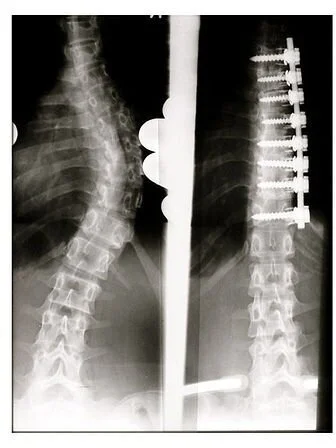

2. Fusion

Spinal Fusion (Weiss HR, Goodall D. Scoliosis. 2008 Aug 5;3:9. PMID: 18681956. doi:10.1186/1748-7161-3-9)

If the spine has been fused it may not be possible to reach the epidural space. The location of the fusions and what materials were used in the procedure will affect whether you can receive an epidural.